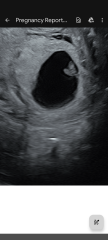

• is it ok if my twins look like they're almost overlapping a bit on the ultrasound? They're in a love heart / V shape and the instrusive thinker in me is worried this could mean conjoined even though I know the chance of this is very small.

I'm being scanned again by our fertility clinic next week when I'll be 8w but any help with these questions would be SO appreciated as I've got no healthcare professionals to turn to yet. Scan photos attached too.

Thank you so much for taking the time to reply to my ramblings! Hopefully next Monday's scan at 8w I'll get a clearer idea of what's next then. I'll definitely check out Twins Trust too. I'm also relieved to hear you also had that same worrying thought. On the pic where they measure the two of them I think I can see a tiny gap, but I've stared at those ultrasounds in absolute disbelief for so long this week I think I'm going cross eyed! I hope, despite your complications, all is well with you and your two 🙂

It's hard to tell from your photos but does look like they share a sac - won't know until they are a bit bigger. But you'll get lots of extra scans and generally NHS will advise they are born earlier - tends to be a sliding scale 37 weeks for di di 36 weeks for mo di and 35 weeks for mo mo

@boulevardofbrokendreamss sorry to hear you had lots of complications, hope everything is OK now. I am worried about mo-mo but hopefully having two yolk sacs (although one gestational sac) is a good sign we might have mo-di although they're so snuggly it's hard to believe there's a membrane between them!